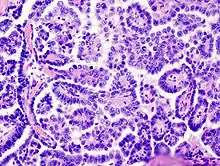

Medium power slide of ovarian serous adenocarcinoma stained using haematoxylin and eosin

Papillary serous cystadenocarcinomas may exhibit psammoma bodies upon histopathology.[3]